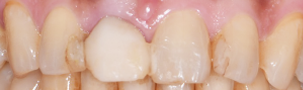

前歯が割れてしまってインプラントをご希望で来院された患者様です。

前歯に亀裂が入ってしまっており、抜歯後、インプラント治療を行いました。

X-ray

非常に審美的な治療が出来ました。

当院では難しい前歯のインプラントも違和感なくきれいに処置することが出来ます。

| 治療期間 | 1年6か月 |

|---|---|

| 費用 | インプラント 37万円 骨造成 15万円 補綴 ジルコニアクラウン 15万円 |